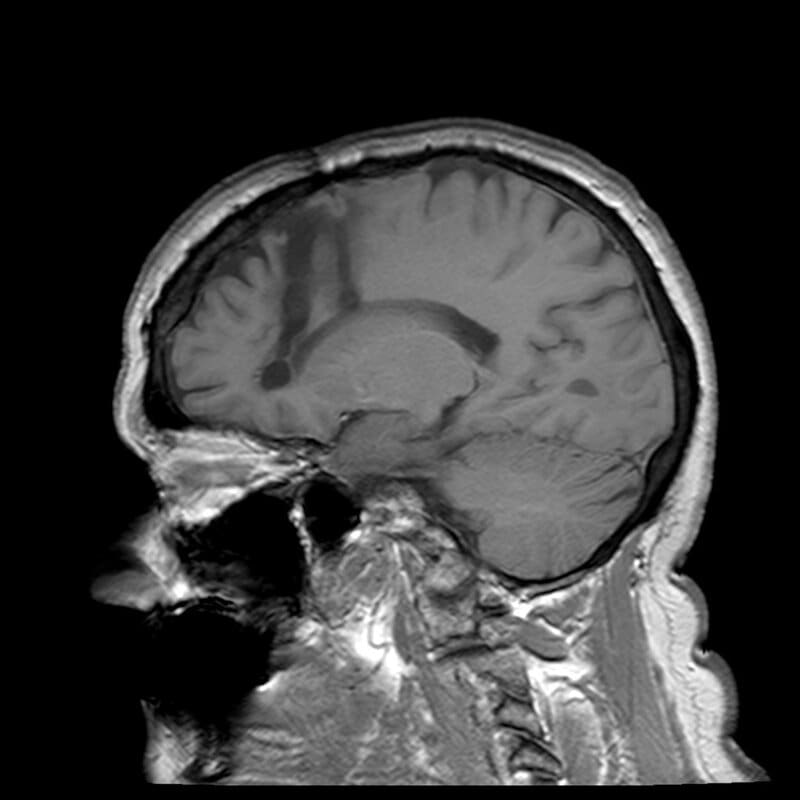

Original caption: Dr. Walter Freeman, left, and Dr. James W. Watts study an X ray before a psychosurgical operation. Psychosurgery is cutting into the brain to form new patterns and rid a patient of delusions, obsessions, nervous tensions and the like. Source: Photography Harris A Ewing / Wikipedia